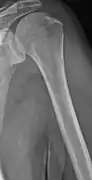

Humerus with multiple myeloma lesions

Same humerus before, with just subtle lesions

The diagnostic examination of a person with suspected multiple myeloma typically includes a skeletal survey. This is a series of X-rays of the skull, axial skeleton, and proximal long bones. Myeloma activity sometimes appears as "lytic lesions" (with local disappearance of normal bone due to resorption) or as "punched-out lesions" on the skull X-ray ("raindrop skull"). Lesions may also be sclerotic, which is seen as radiodense.[70] Overall, the radiodensity of myeloma is between −30 and 120 Hounsfield units (HU).[71] Magnetic resonance imaging is more sensitive than simple X-rays in the detection of lytic lesions, and may supersede a skeletal survey, especially when vertebral disease is suspected. Occasionally, a CT scan is performed to measure the size of soft-tissue plasmacytomas. Bone scans are typically not of any additional value in the workup of people with myeloma (no new bone formation; lytic lesions not well visualized on bone scan).